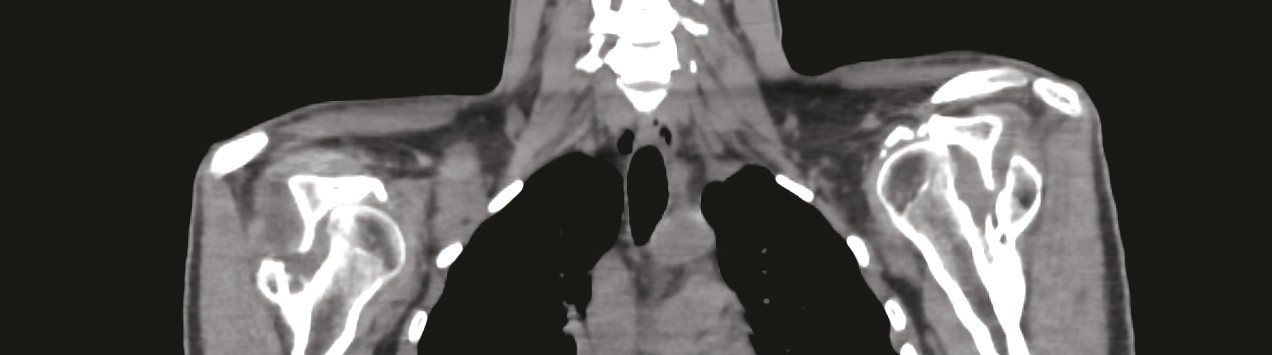

Un homme de 21 ans est admis en service de réanimation pour convulsion fébrile, quelques semaines après avoir été rapatrié d’une mission en zone d’endémie palustre pour des crises convulsives. Le diagnostic d’un accès palustre à Plasmodium falciparum est confirmé. L’évolution est marquée par la survenue d’un déficit moteur et sensitif au niveau des deux membres supérieurs avec une amyotrophie des muscles de la ceinture scapulaire ; un syndrome de Parsonage-Turner post-infectieux est suspecté (fig. 1 ). Un électromyogramme, une imagerie par résonance magnétique (IRM) du plexus brachial (fig. 2 ) et un scanner des épaules sont en faveur d’une luxation antérieure post-convulsive des deux épaules (fig. 3 et 4 ).

Les radiographies standard contribuent à poser le diagnostic ; le scanner permet d’appréhender le siège exact et l’étendue des lésions osseuses de passage antérieur.